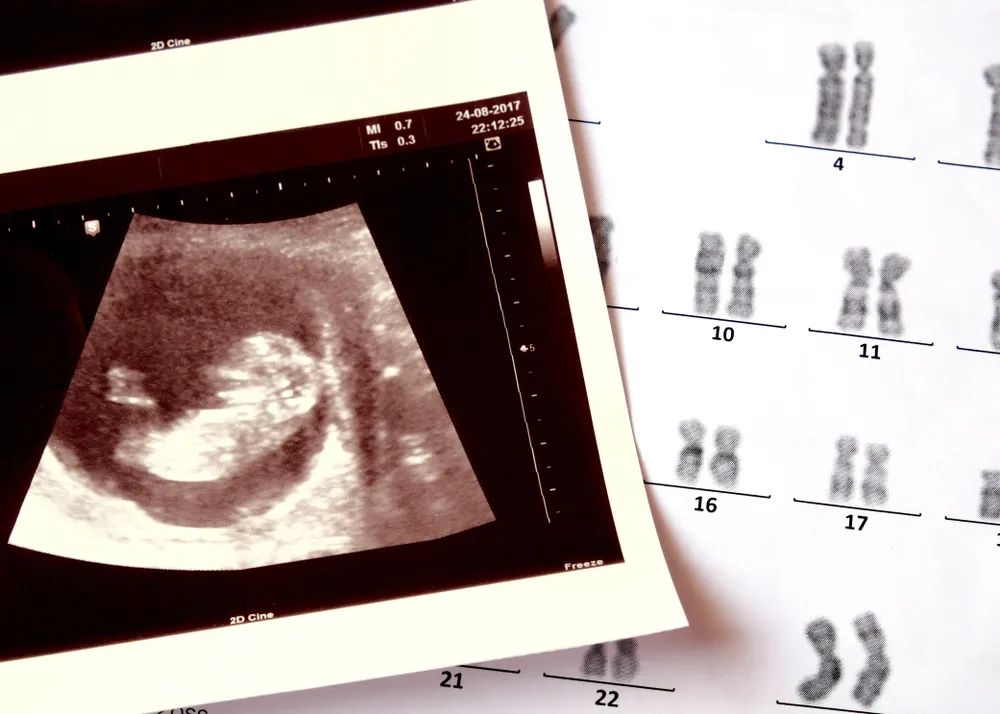

当生育不能自然来临,一些人被下了「不孕」的诊断,当生育的环节需要医学的介入、付出额外努力时,可能,我们才会重新审视生育本身,窥见「成为母亲」可以是一个选择,看到女性需要为生育本身承担的职责与焦虑。

很多生育障碍的夫妇,寄希望于试管等生殖技术,来改变生活状态,但技术的不确定,让焦虑卷土重来,很多女性被身体受创与生殖焦虑反复拉扯。

曾纪琪夫妇正在尝试试管婴儿。

根据中国人口协会、国家计生委联名发布的《中国不孕不育现状调研报告》显示,中国的不孕不育发病率在 12.5%~15% 左右,患者人数超过 4000 万,占到全部育龄人口的 12.5% 。

为了尽可能排除那一点点因素,曾纪琪和黎晓都选了更明确的方案 —— 试管。

曾纪琪决定做试管之后,开始进入各种各样的试管群和求子论坛和不同的人聊天,她看到群里有不少人经历过四五次的、甚至有十几次还没有成功的,很多人是从安徽、苏北一些县和农村来到南京租房子做试管,最低费用的一代试管,一次也需要 4~5 万,很多人举债十几万仍未成功,她想给自己打个心理上的预防针。

医生让曾纪琪先促排卵,这意味着每一天她都必须早早地去医院打针、注射激素,再抽血查看激素水平;每一天都要去做 B 超,查看卵泡生长的情况;每一天都要屁股上打一针,肚子上打两针。算下来就是每一天至少要挨上三针,再加上一针抽血。

一关一关地过:等卵泡长到合适的时机,才到可以去取卵;取卵成功之后,要再等待卵子和精子结合成功,在这之后才能真正地进入移植期。